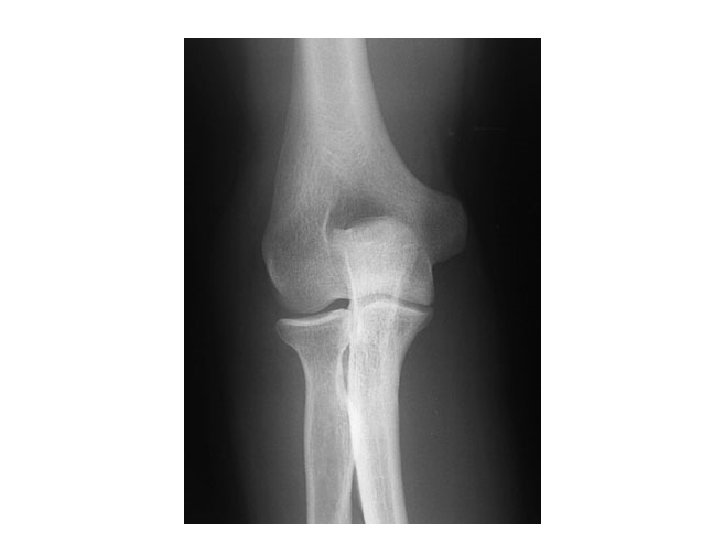

ELBOW

X RAY

Olecranon fossa medial epicondyle Lateral epicondyle capitulum trochlea Radial head Radial teberosity ulna